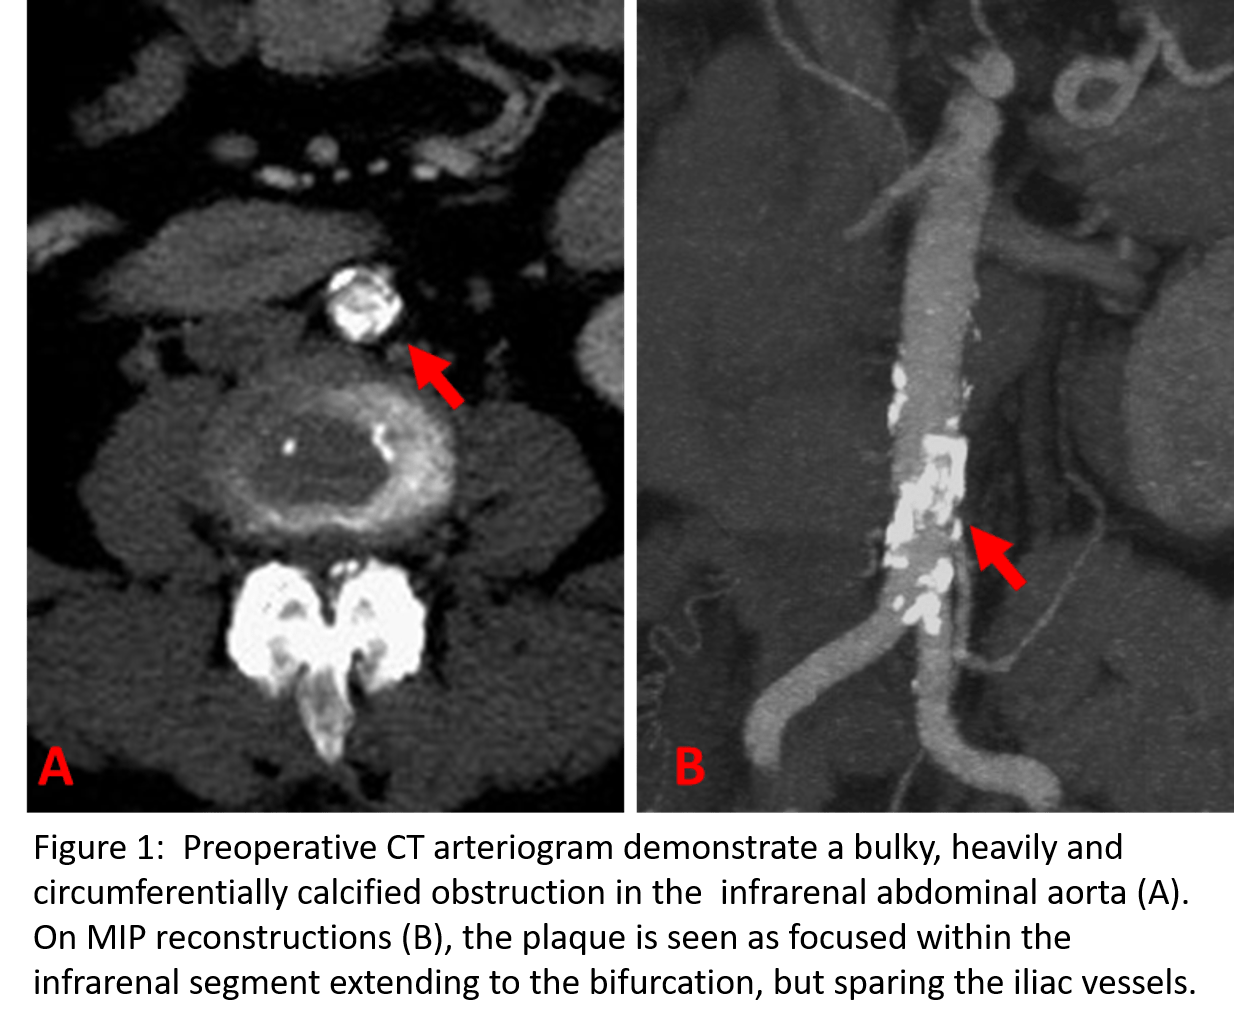

A 61-year-old female presented with a two-month history of right foot pain and discoloration of the first and fifth toe. On questioning, she also noted a history of significant short distance thigh and buttock claudication for the last several months. She was relatively healthy at baseline with a history of hypertension and hyperlipidemia,but a substantial smoking history of two and a half packs per day for 30 years. Her surgical history was notable only for a previous back surgery. On examination, she had reddish discoloration of her right first and fifth toes. She also had no palpable femoral or distal lower extremity pulses. Noninvasive vascular testing revealed flattened pulse volume recording bilaterally from the high thigh to the digit suggesting significant aortoiliac disease. A CTA of the abdomen and pelvis with runoff was obtained which showed a nearly occlusive coral reef-like plaque isolated to the distal aorta just above the bifurcation with some mural thrombus extending proximally close to the level of the renal arteries and essentially normal iliac arteries and distal runoff. (Figure 1) Preoperative testing included a normal stress test.